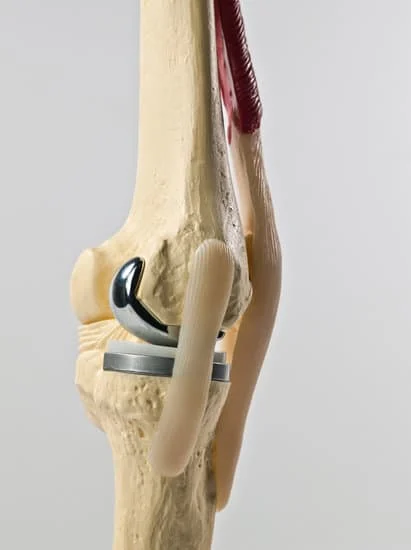

Quality and affordable healthcare has long been the essence in the field of medical sciences & treatment. Every patient expects an early diagnosis and a planned approach to treatment procedures with affordability and access to quality healthcare. Knee replacement, Hip replacement, Fracture treatment are being done by Dr.P.Sankaralingam at very affordable costs without compromising on quality.

Dr.P.Sankaralingam M.S(ortho)., DNB (ortho).,MNAMS is an experienced senior consultant Orthopaedic surgeon who does about 350 joint replacement surgeries per year in addition to treatment of Trauma cases.

Standard Hospital, Chennai’s Centre of Excellence for Orthopaedics offers minimally invasive surgeries for faster recovery.